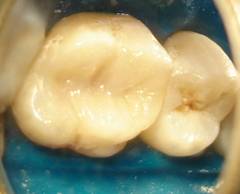

A restauração de dentes com resinas compostas (materiais com a

cor dos dentes) é hoje em dia um tratamento muito procurado,

não só para restabelecer a função, mas sobretudo para repor e

resolver problemas estéticos.

Antes![]() |

Depois![]() |